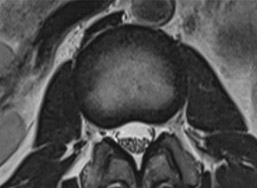

정상 척추관

좁아진 척추관